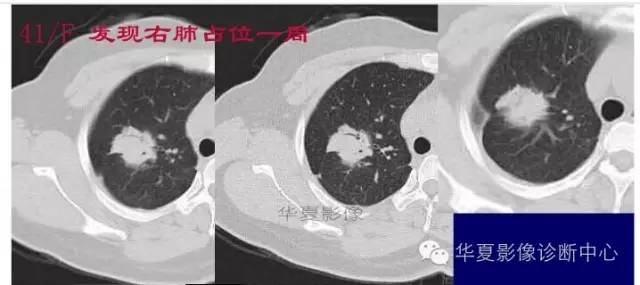

这一例是否GGO成分几乎没有

基本是实性的

那就按实性的分析

胸膜凹陷,分叶征

大家仔细看看这个中央不强化的腔内壁

你会发现内壁强化明显,边界清楚

一般这是炎性的脓腔,内层是肉芽肿,明显强化,分界清楚

癌肿的坏死一般是缺血性的,是肿瘤生长速度过快,中央带的血管受挤压,中央供血不足坏死的,一般边界模糊

内有内层强化,不会这么清楚

这是两者坏死的差异

内带强化带,边界清楚

但是这个其实整体看起来不是分叶征

只是一个一个的凸起